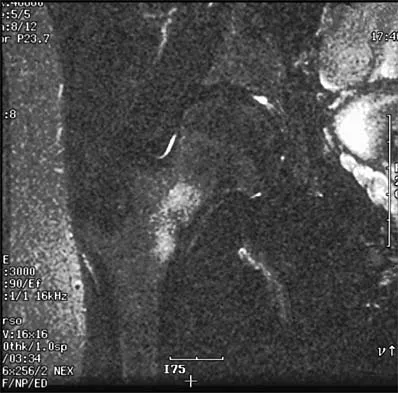

A 35-year-old woman dislocated her right shoulder in a fall from a step stool several months ago. She now reports several painful recurrences. Examination reveals anterior and inferior apprehension that reproduces her symptoms. An MRI scan is shown in Figure 17. Management should consist of

Explanation